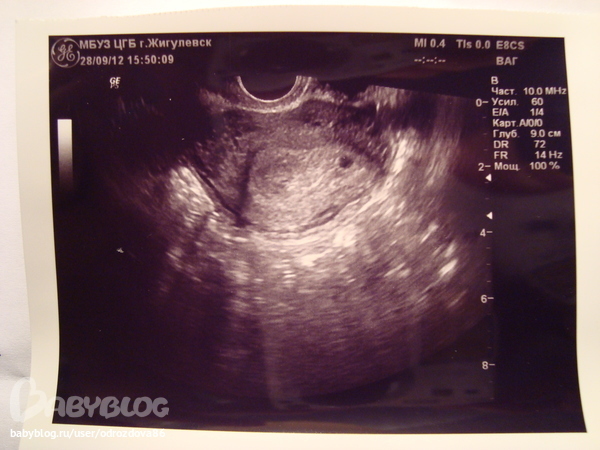

Ну беспокойство вызвало что врач Узи сказал что оно расположено очень близко к трубе и естественно сроки кто прав по срокам врач гинеколог или врач узи как писала выше срок у гинеколога 6 неделек, по узи 2 недели

Плодное яйцо в полости матки - значит беременность маточная.